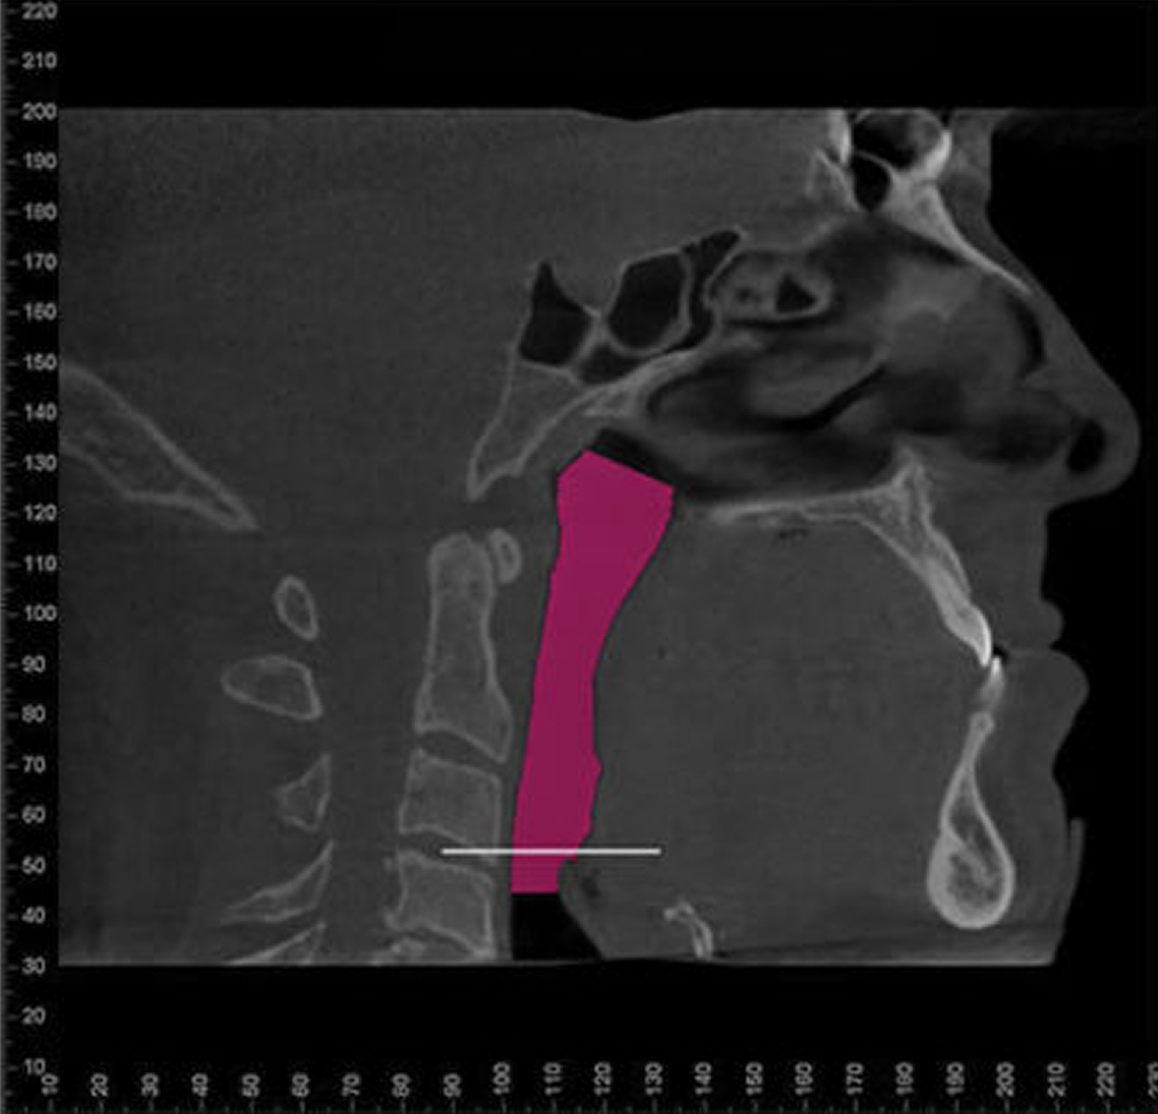

For many patients, an orthodontic intervention in Highland, NY or Ramsey, NJ can improve and sometimes eliminate these risks. Below are pictures of an OSA patient that benefitted from orthodontic treatment’s life-changing effects at Van Vliet & Ganz Orthodontics.

867% Airway Enhancement